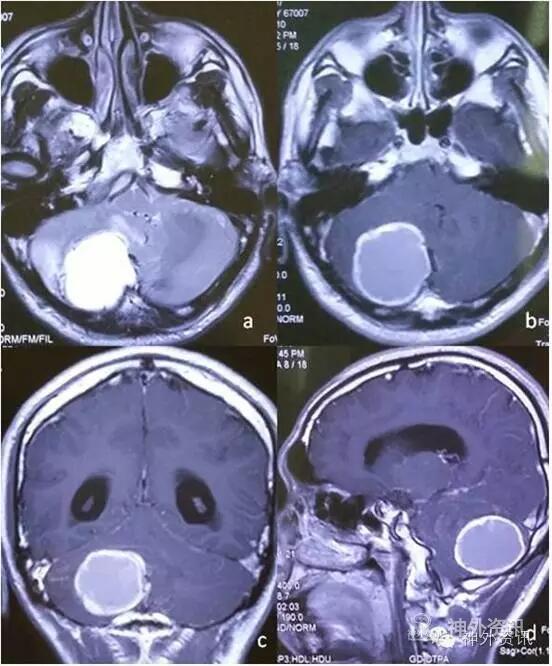

患者3年半前无明显诱因下出现反复头痛不适,严重时伴有喷射性呕吐。头颅MRI检查提示右侧小脑可见类圆形囊实性团块影,边界尚清,直径约35mm,囊性部分呈T1稍高信号,T2高信号,增强扫描边缘及实性部分明显强化,囊性部分不强化;团块周围可见片状呈长T1长T2信号,诊断为“右小脑肿瘤”(图1)。行开颅肿瘤切除术,术中见右小脑凸面肿瘤,色红、血供丰富、质地软、有完整包膜,穿刺抽出暗红色陈旧性血液,沿肿瘤周围分离肿瘤并切断供血血管,完整切除肿瘤。

图1. 增强MRI显示,右侧小脑可见类圆形囊实性团块影,增强扫描边缘及实性部分明显强化。可见周围片状长T2信号。